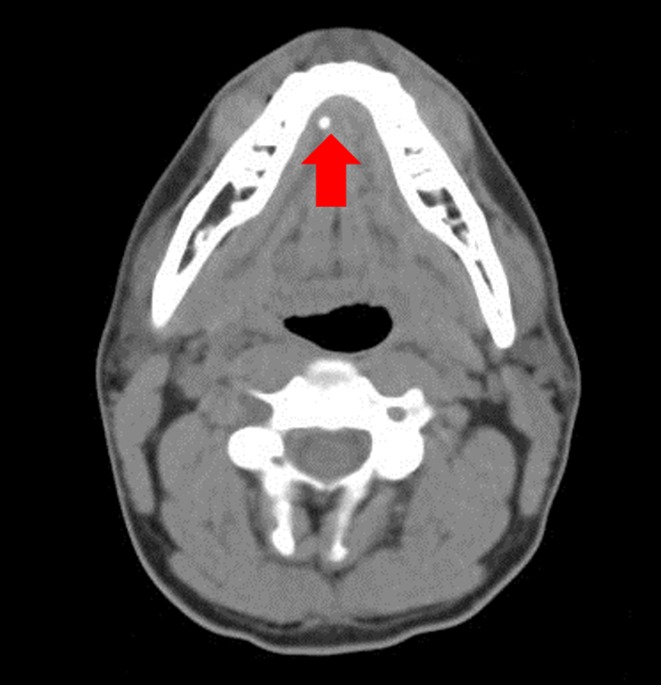

Sialolithiasis

| Diagnosis |

- Stone palpable in floor of mouth = Submandibular sialolithiasis

- Most common salivary gland disorder overall: Sialolithiasis (80% in submandibular gland)